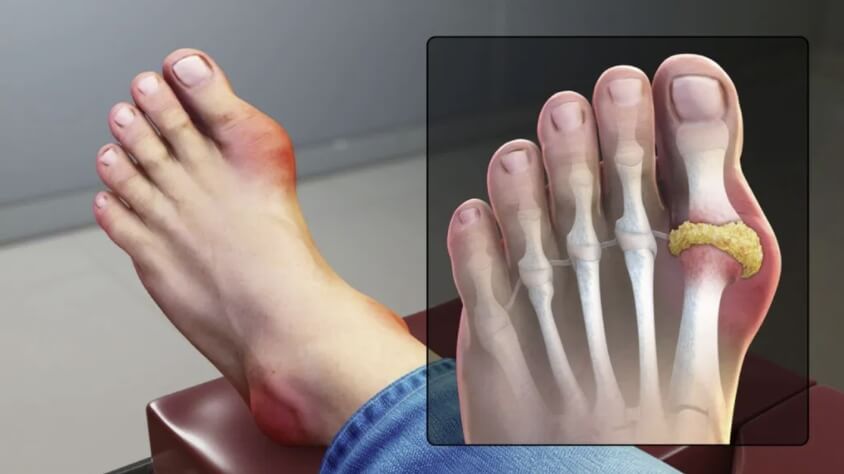

통풍은 요산이 너무 많아져서 혈액 내에 결정으로 축적됨으로써 발생하는 대사성 질환입니다. 요산은 일반적으로 신장을 통해 체내에서 배출되지만, 신장 기능이 저하되거나, 요산 생성이 과다한 경우에는 요산이 혈액 내에 축적되어 결정으로 형성됩니다. 이 결정이 관절 부위에 쌓이면 염증이 발생하여 통풍이 발생합니다. 따라서 상당히 고통스러운 통풍에 대해 보다 자세히 알아보기 위하여 원인, 증상, 치료방법 등을 자세히 알아보겠습니다.

통풍은 대개 발적을 침범하며, 발적 주위의 관절에서도 통증을 일으킬 수 있습니다. 대개 발목, 무릎, 발가락 등을 포함하며, 통증은 심할 때 걷는 것이 거의 불가능할 정도로 심해질 수 있습니다.

염증

급성 통풍 발작은 관절 내부에서 염증이 발생합니다. 이는 염증을 일으키는 화학 물질이 적출물로 발적 주위에 축적되기 때문입니다. 염증은 일반적으로 통증, 붓기, 붉어짐 등을 초래할 수 있습니다.

- 요산 결정이 관절 주변에 축적되어 통풍을 유발하는 경우, 요산 결정을 제거해야 합니다.